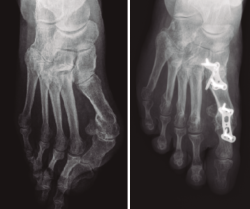

Material y métodos: se revisaron las radiografías de 14 pacientes con HV severo (AIM ≥ 15°) tratados mediante técnica de osteotomía distal metatarsiana asociada a la artrodesis MTF (seguimiento medio: 15 meses). Una revisión independiente realizó las mediciones. Las variables del estudio han sido: el AIM prequirúrgico (AIM preQ), el AIM posquirúrgico (AIM posQ), la diferencia y el cociente de los AIM preQ y AIM posQ. Se han comparado los pacientes con TQC frente a la artrodesis MTF aislada (utilizando series publicadas en la literatura).

Resultados: Grupo A: pacientes de TQC. Grupo B: pacientes tratados con artrodesis MTF aislada. Los AIM preQ son iguales en ambos grupos. Los ángulos posQ en el grupo A son 4,194° y 9,9° en el grupo B (p < 0,001). La TQC logra reducciones del AIM de 14,253° de media en el grupo A frente a los 8,489° de reducción del AIM conseguidos en el grupo B por la artrodesis MTF aislada.

Conclusiones: el tratamiento quirúrgico combinado (osteotomía metatarsiana más artrodesis MTF) consigue mayor corrección radiológica del AIM que la artrodesis MTF aislada.